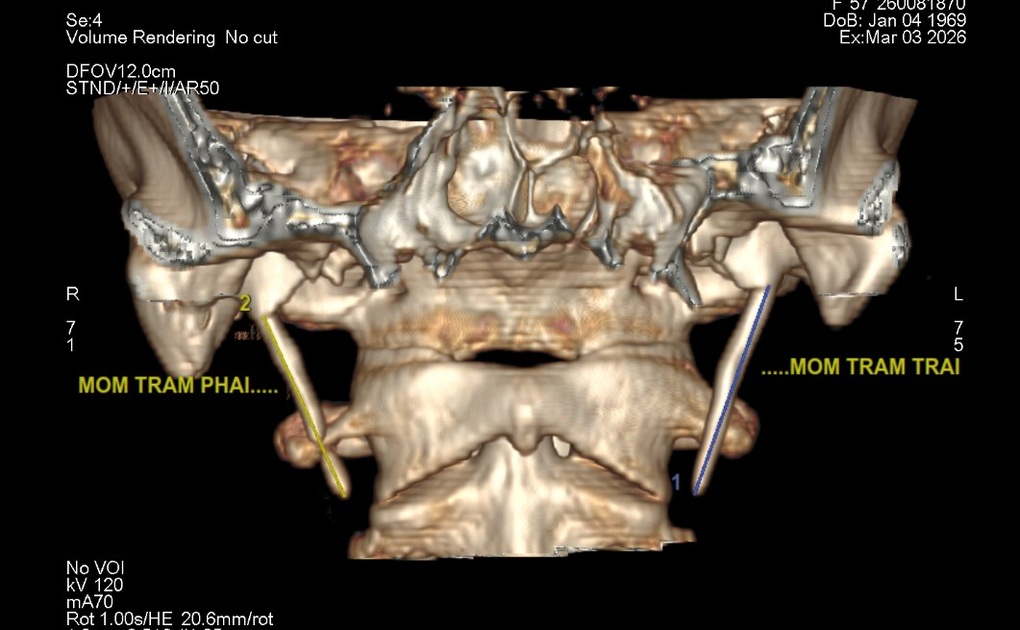

Không nằm ngoài dự đoán, kết quả chụp cắt lớp vi tính của người bệnh cho thấy xương mỏm trâm hai bên dài tới hơn 5cm, gần gấp đôi so với mức bình thường chỉ 2-3cm. Sự kéo dài bất thường này đã gây chèn ép vùng họng, là nguyên nhân trực tiếp dẫn đến các cơn đau nhói kéo dài suốt nhiều năm.

Xương mỏm trâm hai bên của cô D qua hình chụp CT 3D (Ảnh: BVCC).